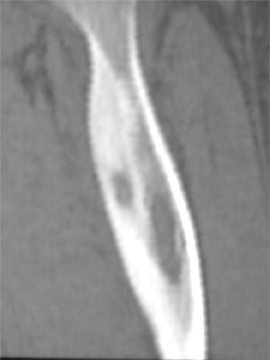

Malignes :

Ostéosarcome,

sarcome d’Ewing, autres cancers